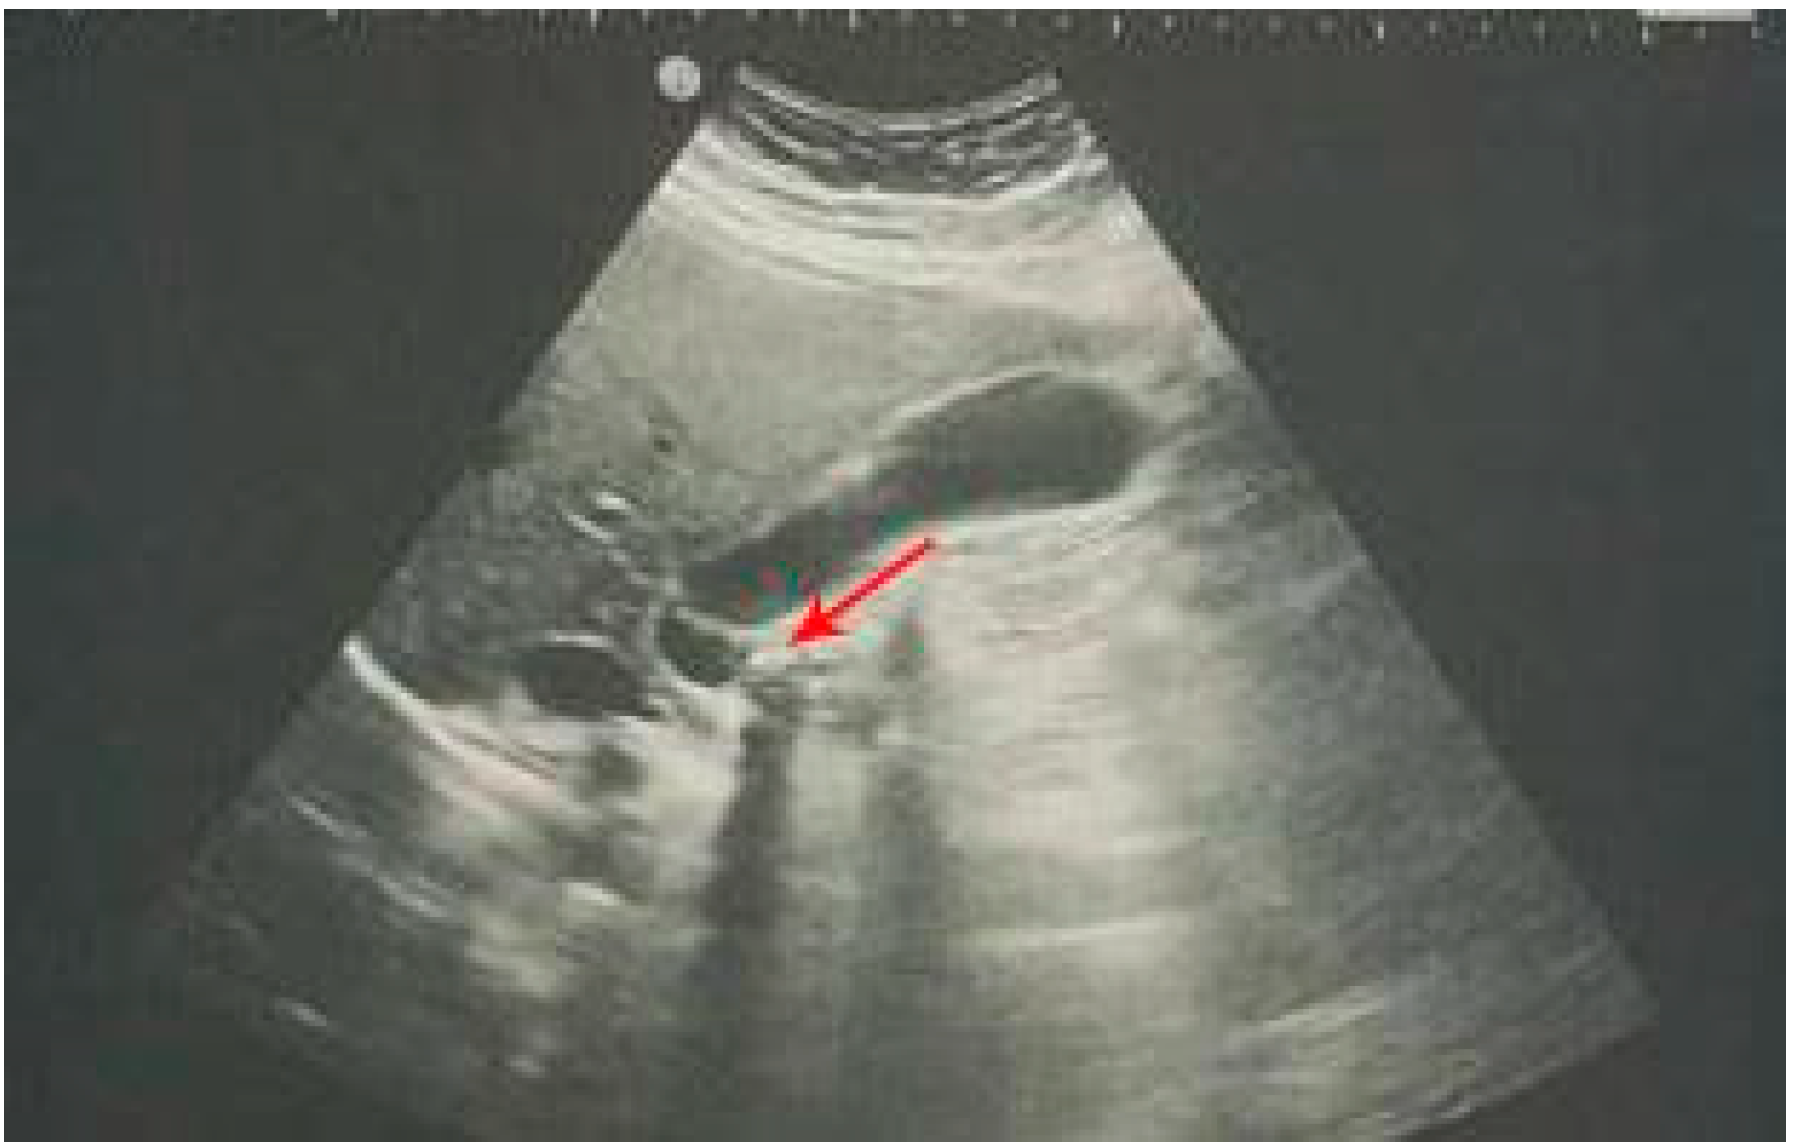

5. Urolithiasis and Hydronephrosis